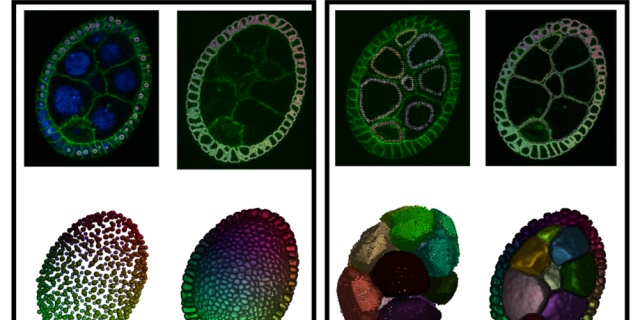

本文详细介绍了如何使用ImageJ进行3D图片的重构和体积测量。通过3D Viewer和Volume Viewer插件实现3D可视化,针对CT或MRI等Stack图像,调整Z轴步长以正确显示结构。接着,利用3D Object Counter测量3D体积和表面积,通过阈值设置和尺寸过滤确保精确测量。文章提供了详细的步骤和注意事项,适用于生物医学图像的定量分析。

本文详细介绍了如何使用ImageJ进行3D图片的重构和体积测量。通过3D Viewer和Volume Viewer插件实现3D可视化,针对CT或MRI等Stack图像,调整Z轴步长以正确显示结构。接着,利用3D Object Counter测量3D体积和表面积,通过阈值设置和尺寸过滤确保精确测量。文章提供了详细的步骤和注意事项,适用于生物医学图像的定量分析。